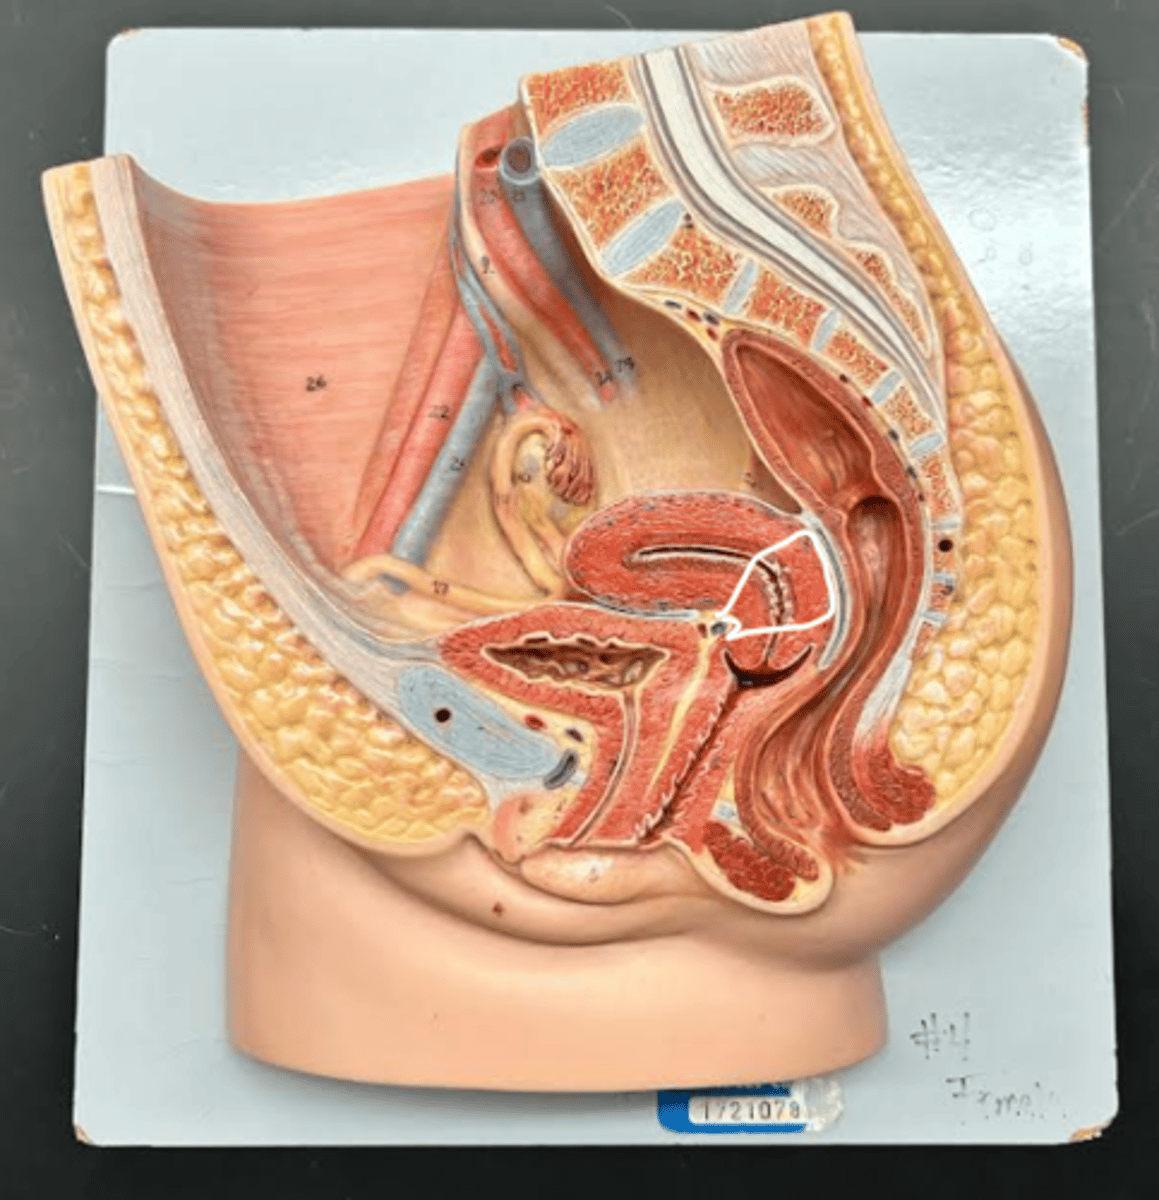

Chapter 29 Anat Phys: Female Reproductive System

Vagina

Vaginal orifice

Hymen

Vaginal fornix

Ovary

Fallopian tube

Fimbriae

Infundibulum

Ampulla

Isthmus

Uterus

Perimetrium

Myometrium

Endometrium

Fundus

Body of uterus

Cervix

Internal os

Cervical canal

External os

Labia majora

Labia minora

Prepuce

Vestibule

Clitoris

External urethral orifice